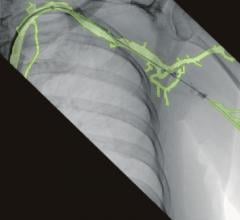

U.S. Electronics Inc. will introduce two new medical-grade high-luminance monochrome LCD displays, offering a full array of features. The new high-contrast USEI/Totoku ME355i2 3 MP and ME253i2 2 MP monitors support a broad range of diagnostic imaging modalities, including CT, MRI and high-speed 3-D image rendering. Utilizing Totoku’s Luminescence Uniformity Equalizer technology, both models provide consistent light intensity across the entire display face, eliminating uneven brightness at the periphery. An 11.9-bit lookup table (LUT) delivers ultra-high grayscale DICOM conformance for a distortion-free image.